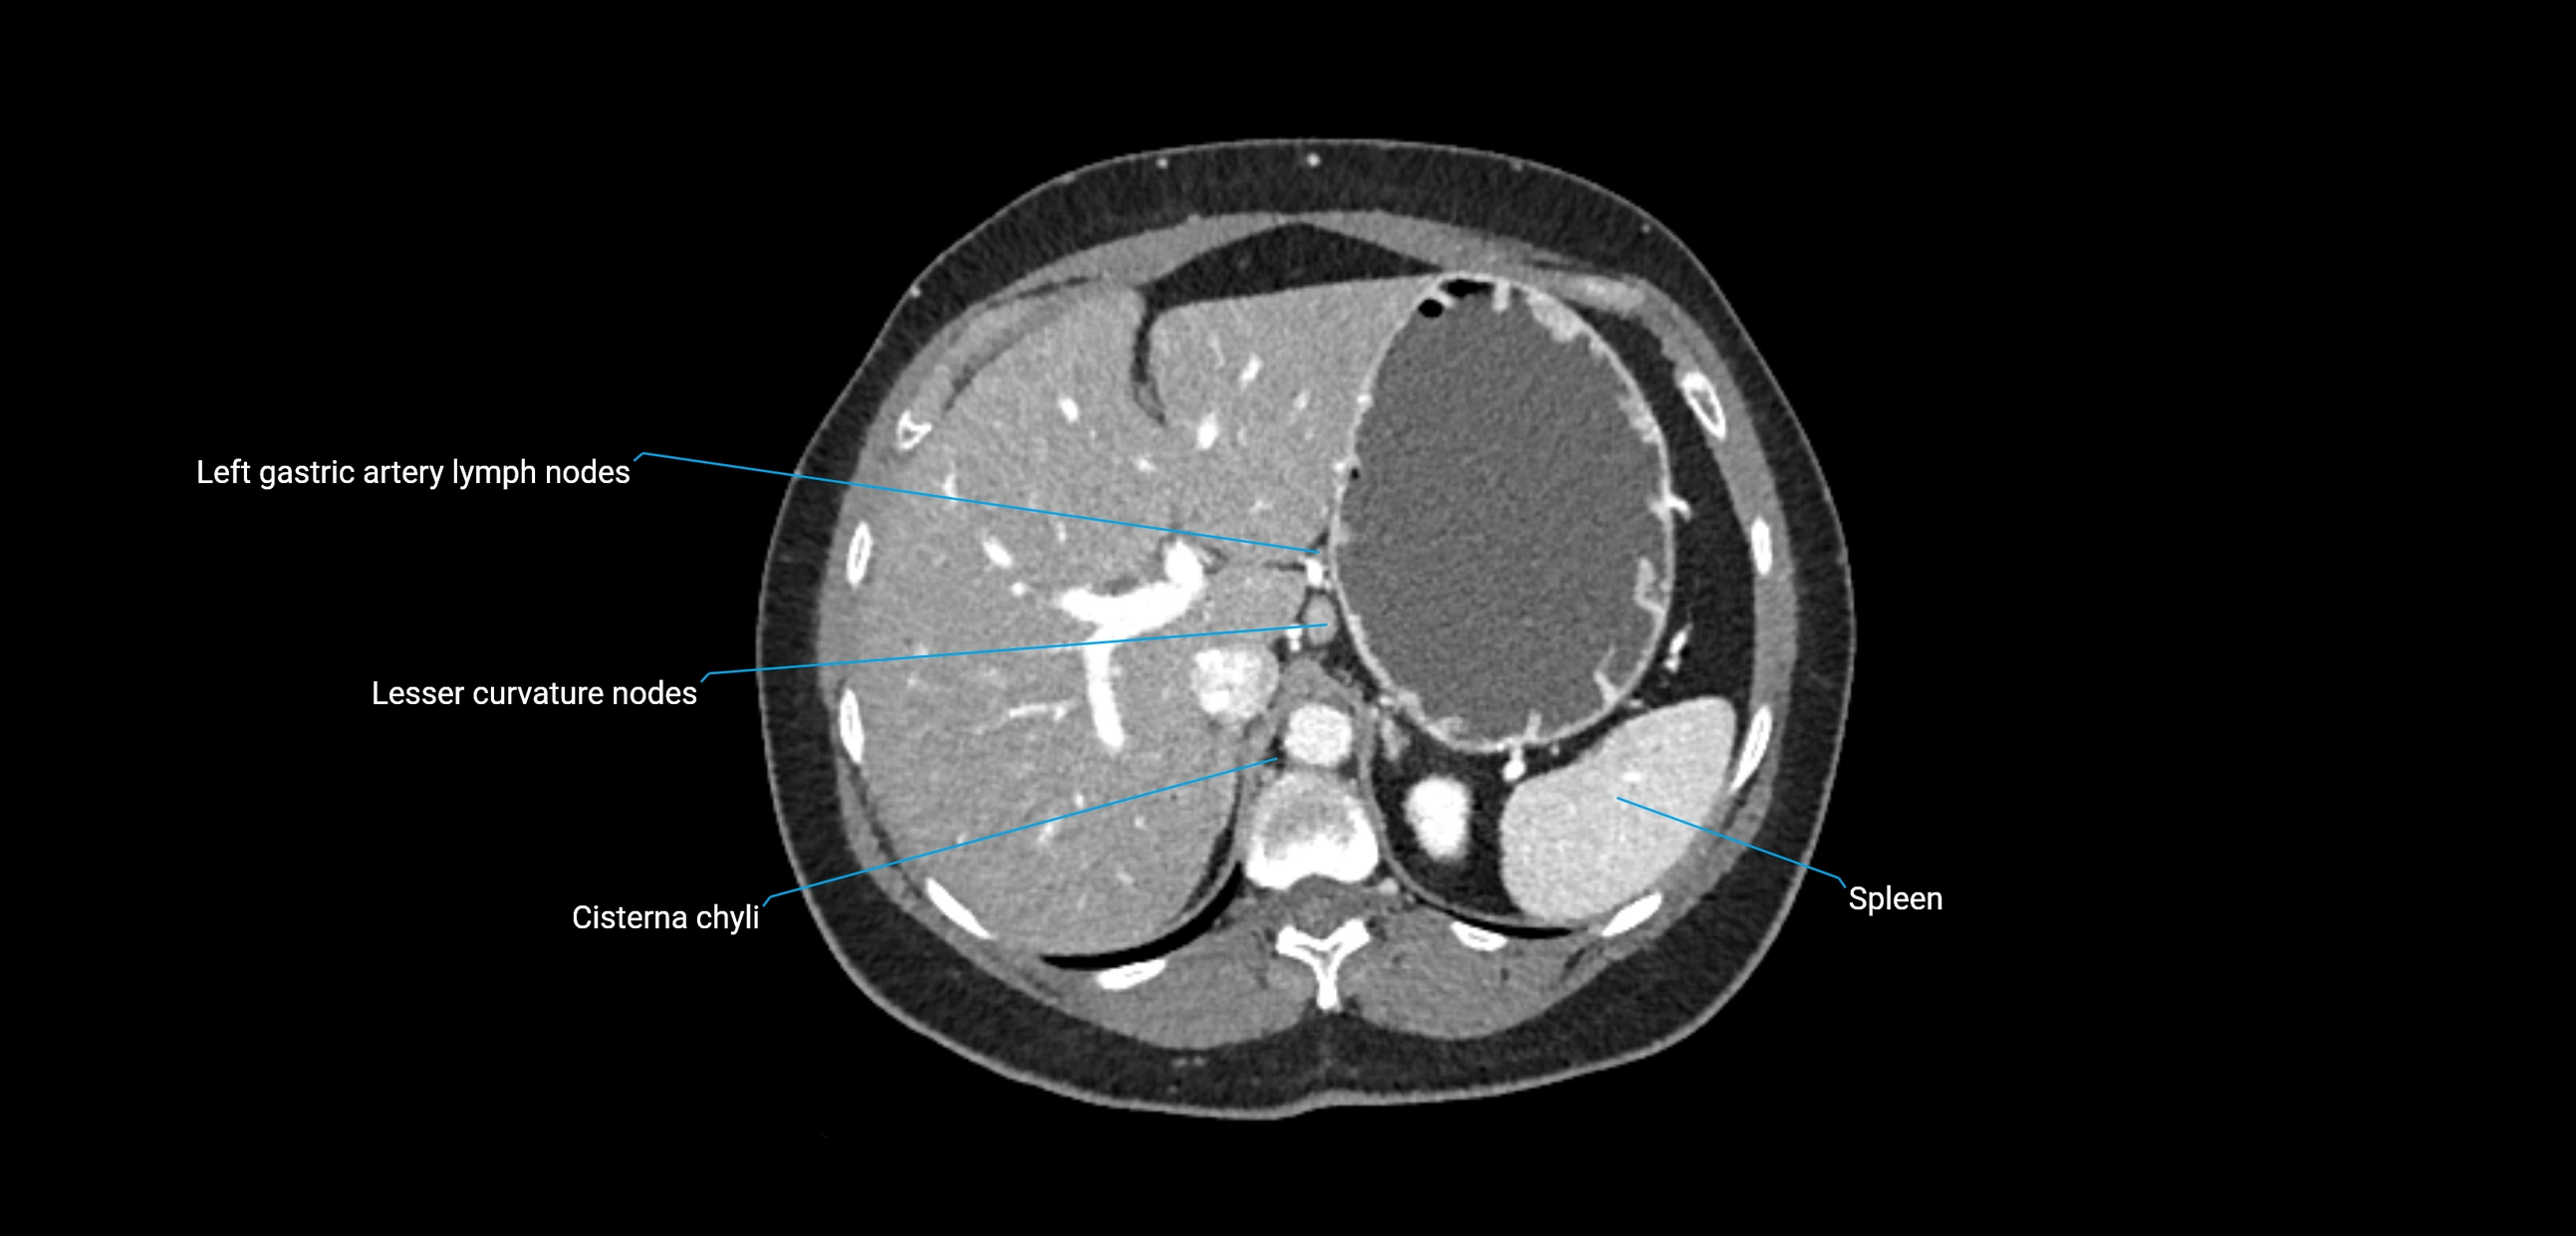

MRI images

image